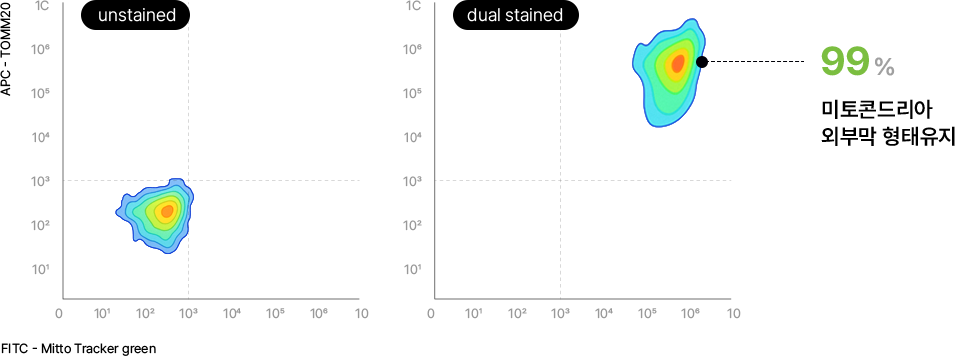

세포 내 미토콘드리아 분리 가능 및 구조적 손상없음 확인

분리된 미토콘드리아 중 99%의 외부막이 손상되지 않고, 온전한 형태를 잘 유지하고 있음을 확인